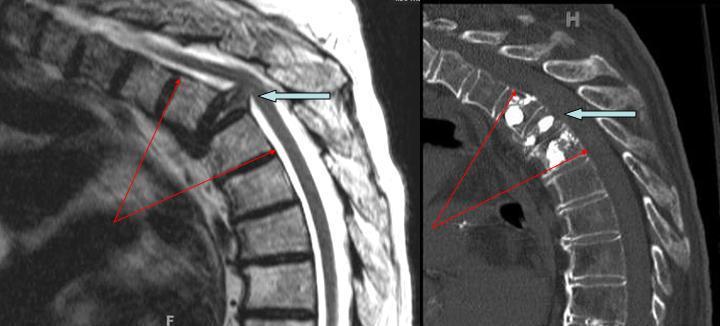

Παρακάτω απεικονίζεται ασθενής με κάταγμα ανώτερης θωρακικής μοίρας με επέκταση στο σπονδυλικό κανάλι. Με γαλάζιο βέλος φαίνεται το κάταγμα που προβάλλει μέσα στο κανάλι (αριστερά), ενώ δεξιά φαίνεται η ανάταξη του κατάγματος και της γωνίωσης (κύφωση) της σπονδυλικής στήλης (σύγκρινε τις κόκκινες γωνίες πριν και μετά την επέμβαση), μετά τη διενέργεια κυφοπλαστικής σε 3 σπονδύλους (τόσο στον υπερκείμενο, όσο και στον υποκείμενο).

Η περίπτωση που αναφέρθηκε βέβαια είναι πιο απαιτητική και δέον να διενεργείται από έμπειρους ιατρούς. Έχουμε δημοσιευσει την εμπειρία μας σε τέτοια κατάγματα στο επίσημο περιοδικό της αμερικανικής ένωσης νευροχειρουργών (http://www.ncbi.nlm.nih.gov/pubmed/21250808).